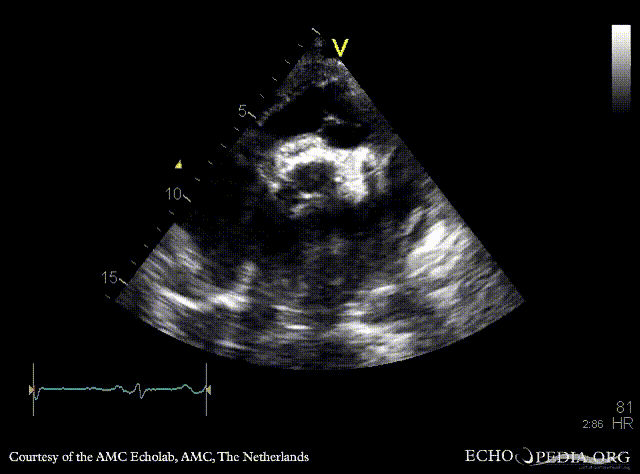

PSAX: aortic bioprosthesis